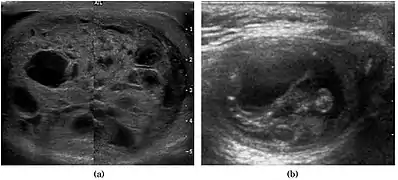

Teratoma Although teratoma is the second most common testicular tumor in children, it affects all age groups. Mature teratoma in children is often benign, but teratoma in adults, regardless of age, should be considered malignant. Teratomas are composed of all three germ cell layers, i.e. endoderm, mesoderm and ectoderm. At ultrasound, teratomas generally form well-circumscribed complex masses. Echogenic foci representing calcification, cartilage, immature bone and fibrosis are commonly seen [Fig. 5]. Cysts are also a common feature and depending on the contents of the cysts i.e. serous, mucoid or keratinous fluid, it may present as anechoic or complex structure [Fig. 6].

Fig. 6. Mature cystic teratoma. (a) Composite Image. Mature cystic teratoma in a 29-year-old man. Longitudinal sonography image of the right testis shows a multilocular cystic mass. (b) Mature cystic teratoma in a 6-year-old boy. Longitudinal sonography of the right testis shows a cystic mass contains calcification with no obvious acoustic shadow.